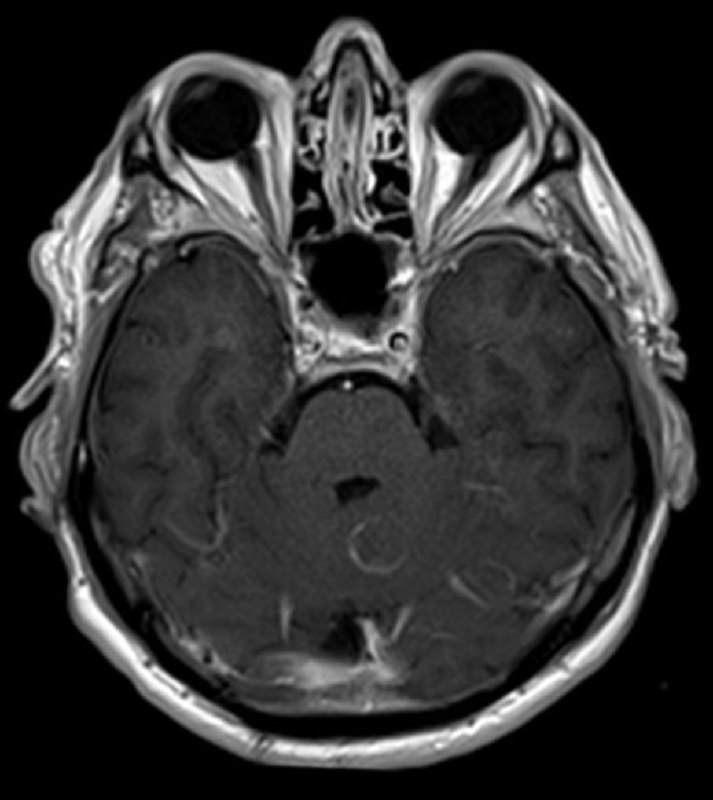

интересный случай! И не менее интересны ваши мнения! Мужчина 74 года.

в декабре 2020 удалена менингиома, а теперь - вот так